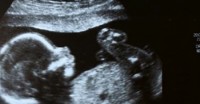

El Pilates durante el embarazo

El Pilates durante el embarazo puede ser una herramienta muy útil para el bienestar de la madr y del niño. Debido al crecimiento del bebé, en los meses del embarazo, los músculos de la pared abdominal se estiran y pueden debilitarse. Los músculos del suelo pélvico también sufren una gran tensión y tienden a estirarse y a descender más en la pelvis, debido al peso del bebé.